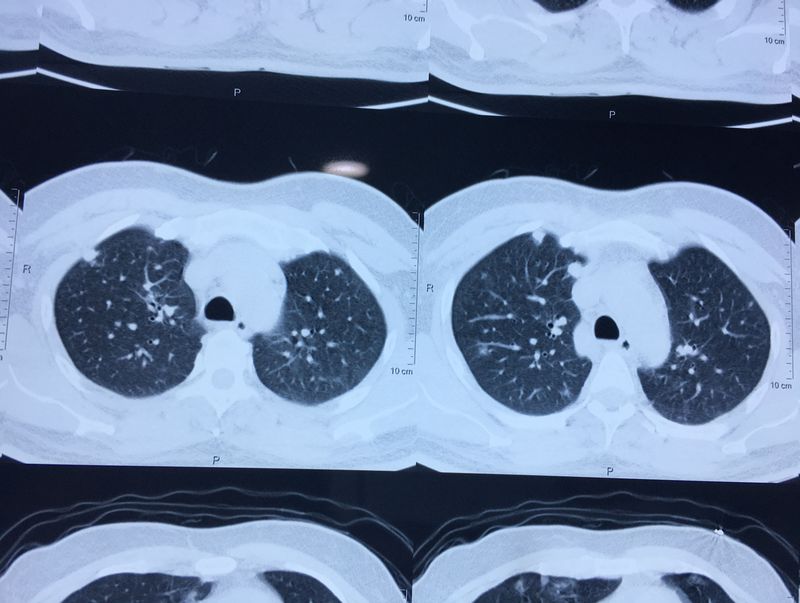

PROSTATE CANCER- METASTASIS (CT LUNG)

CT lung shows small dots.. that indicates the Metastatic (stage4). USG KUB shows that enlarged prostate. FNAC clarified that the individual is suffering from Prostate cancer.